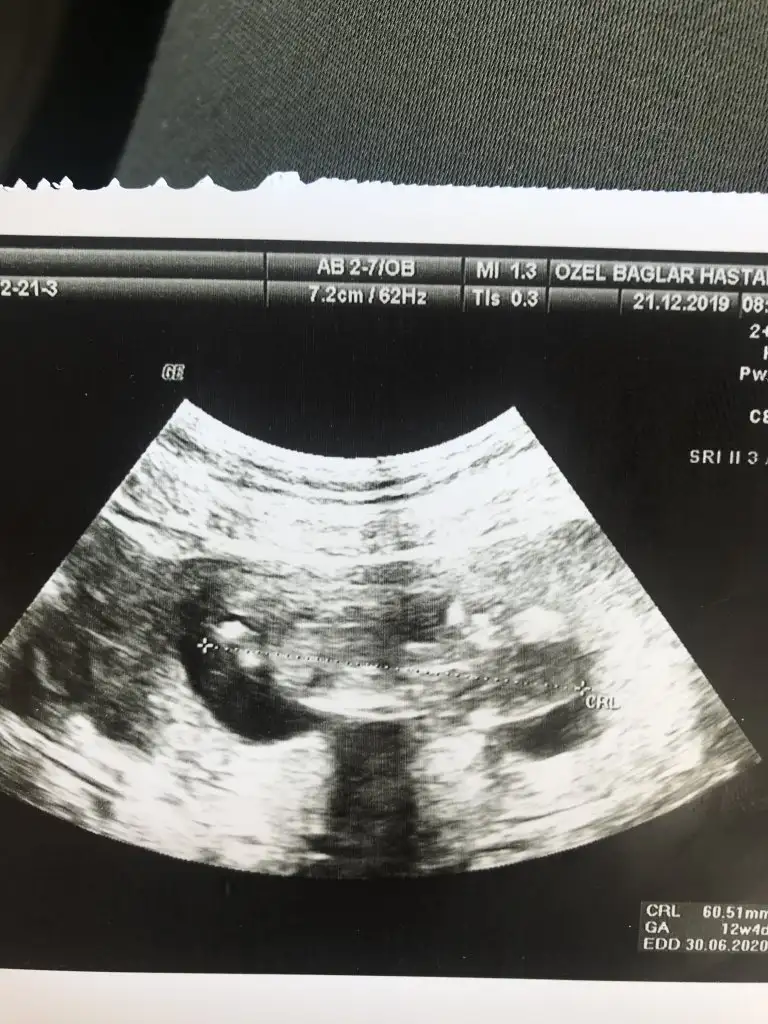

Benim kine de bakar mısınız lütfen

Eklentiler

• 20191221_185839.webp

20191221_185839.webp

28,6 KB · Görüntüleme: 44

• 20191221_185223.webp

20191221_185223.webp

44 KB · Görüntüleme: 44

• 20191221_185211.webp

20191221_185211.webp

38 KB · Görüntüleme: 32

• 20191219_125217.webp

20191219_125217.webp

17,6 KB · Görüntüleme: 37